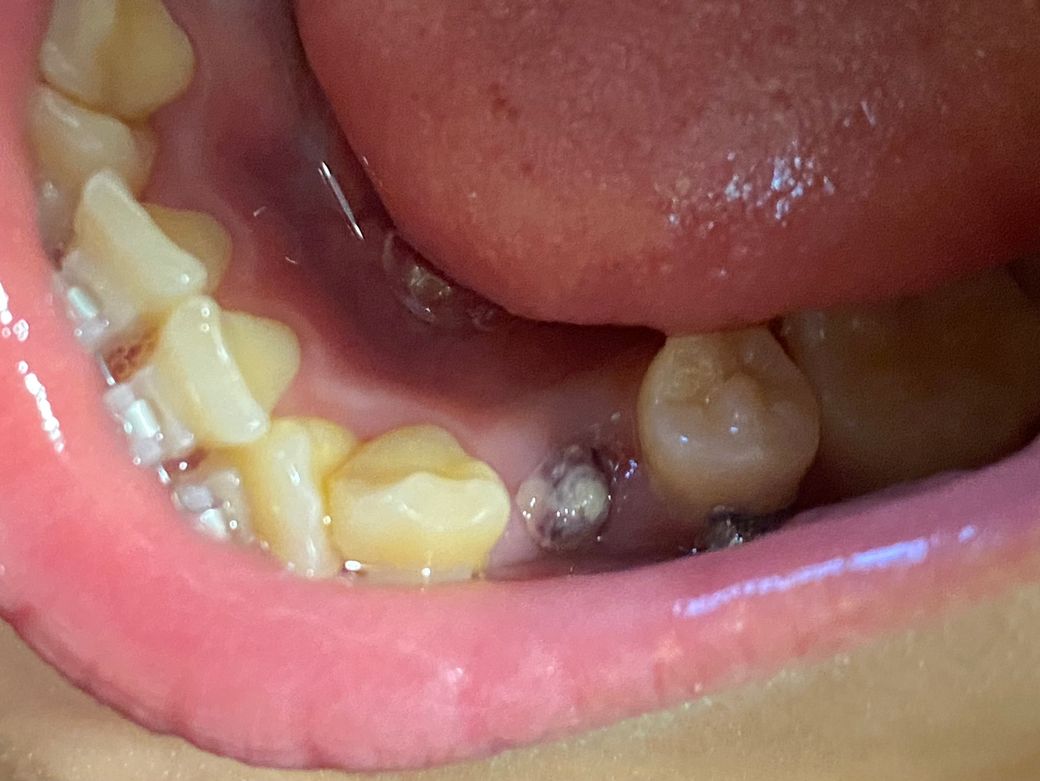

그냥 딱지인가요, 드라이소켓인가요? (사진)

교정때문에 송곳니 뒤 작은 어금니를 위아래로 4개 뽑았는데요!

8/9일에 발치해서 지금 6일차입니다

그런데 다른 세 곳은 괜찮은데 한 곳만 딱지가 조금 이상하게 생겨서 혹시나 드라이소켓인가 걱정이 되네요..ㅠㅠ

검은색은 없고 빨간 피떡 위에 흰색 딱지가 덮여있는 것처럼 생겼습니다

• 1번 째 사진